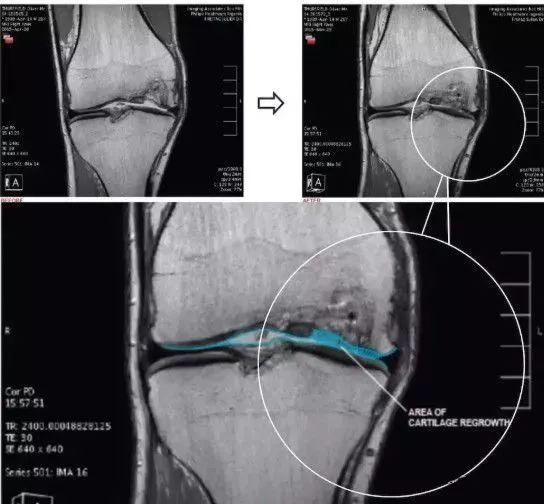

人类的膝关节结构、功能复杂,对于人体来说,膝盖是个十分“微妙”的存在,多用容易磨损,用得太少又容易“生锈”。无论对于运动员,或者是普通人,关节都是最容易在运动中被损伤的组织器官之一。 01 越来越薄的软骨 作为现代人的通病,以膝关节为例,青春期软骨厚度通常为2.5公分,而55岁以后常只剩下0.5公分,甚至更薄而产生破裂、骨刺,这种损伤常常不可逆,带来长期的巨大痛苦。据世界卫生组织提供的数据,50岁以上人群的骨关节病发生率为50%,70岁的老年人发病率高达80%。 现在,很多研究者都在探寻修复关节软骨损伤的方法,目前看来,保护膝盖、预防损伤依然是最好的解决方式。但对于关节损伤的常规治疗方法非常保守:无非通过保护延缓病变进程,或者直接接受关节置换手术而已。 所以一直有很多研究者都在探寻修复关节软骨损伤的方法,例如用干细胞促进组织修复,这些方法也逐渐展现出较为乐观的应用前景。 02 干细胞修复软骨 墨尔本干细胞治疗中心利用患者自身的间充质干细胞注入膝关节治疗膝关节损伤的临床研究是全球范围都较为知名的一项临床试验,这个试验共涉及70名患者,分为30名一组进行对照。最终结果显示,大部分参与试验的患者膝关节功能有了很大的改善:三分之二的患者膝盖疼痛程度和活动受限程度减少了一半,并且保持了一年以上。 术后第二次关节镜检查(图a)。在所有4名患者中,移植区域具有保存完好的透明状软骨结构。4例活检标本的组织学检查结果表明,与邻近关节炎软骨相比,修复效果更好。组织显示存在软骨细胞样细胞,以及透明软骨样结构和基质。所有四个活检标本均为无异位钙化和血管化。并且没有发现炎症迹象。 上图a为治疗前关节镜检查结果,可以看出软骨存在缺损。图b为脂肪间充质干细胞联合PRP治疗,图c为治疗后结果,软骨得到了修复。 在一部来自Youtube上的视频中,医生采集患者自身外周血中的干细胞,联合PRP(富血小板血浆)治疗关节病,患者自述这种疗法有效缓解了疼痛,提高了生活质量。